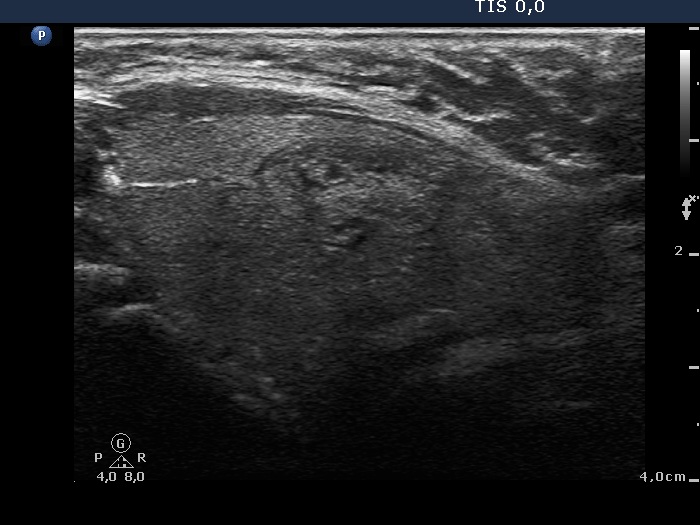

Ultrasonography: There was a partly moderately hypoechoic partly hyperechoic nodule in the left lobe. The nodule displayed halo sign and perinodular blood flow. A hypoechogenic lesion was detected above the thyroid. It met the criteria of a benign, reactive type lymph node: it was homogeneous, the hilum was intact and well-seen and the vascularization was not irregular.

Cytology was performed and resulted in a benign colloid goiter and a benign reactive lymphoid pattern, the thyroid nodule and the lymph node, respectively.